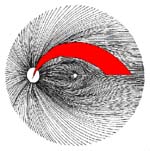

The temporal raphe of the human retina Amer.J.ophthal. 62:926/1966, popsal předěl ve vrstvě nervových vláken temporálně od makuly mezi horní a dolní polovinou sítnice.